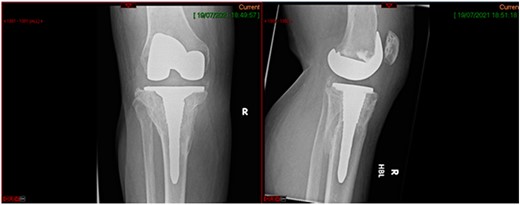

This case report follows a 67-year-old gentleman who sustained a Schatzker VI fracture of his right tibia after falling 2 m from a ladder (Fig. 6). The injury was closed and neurovascularly intact; he was managed initially in a neighbouring health board with a bridging external fixator because of the high degree of comminution. He was referred to the current institution; and at a routine review 3 weeks post-injury, it was noted that a pin had fractured. The external fixator was removed, and he was converted into an above knee cast. He progressed to a Sarmiento cast and then a range of motion brace at 12 weeks. Partial weight bearing was permitted, and he received physiotherapy. He was kept under regular review and the fracture had united (Fig. 7); he was noted to have a range of movement of 10°–60° with healed pin site wounds. At 8 months post-injury, he underwent total knee arthroplasty utilizing a posterior stabilised Depuy Synthes (Warsaw, In) Attune revision tibial metaphyseal sleeve and stem, and femoral component without sleeve or stem. The patient had an uncomplicated recovery and kept under routine review in the outpatient clinic. At 6 months’ review, the patient had a range of motion of 0°–105°, fully healed wound and reported a significant improvement in pain. The patient used no walking aids, and the Oxford Knee score was 40 (Fig. 8).